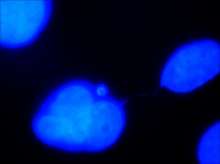

| DAPI staining allows for visualization of deoxyribonucleic acid portions of the two daughter cells. The thin “string-like” DNA connecting them is defined as a chromatin bridge. | |

Chromatin bridge is a mitotic occurrence that forms when telomeres of sister chromatids fuse together and fail to completely segregate into their respective daughter cells. Because this event is most prevalent during anaphase, the term anaphase bridge is often used as a substitute. After the formation of individual daughter cells, the DNA bridge connecting homologous chromosomes remains fixed. As the daughter cells exit mitosis and re-enter interphase, the chromatin bridge becomes known as an interphase bridge. These phenomenon are usually visualized using the laboratory techniques of staining and fluorescence microscopy.[1][2]

Chromatin bridges are easiest and most readily visible when observing chromosomes stained with DAPI. DNA bridges appear to be a blue, “string-like” connection between two separated daughter cells. This effect is created when sticky ends of chromosomes remain connected to one another, even after mitosis. A chromatin bridge may also be observed using indirect immunofluorescence, in which anti-tubulin emits a green coloration when bound to microtubules in the presence of UV light. Because microtubules maintain the positions of the chromosomes during mitosis, they appear to be densely pinched between the two dividing, daughter cells. Chromatin bridges can be difficult to locate utilizing fluorescence microscopy, as this phenomenon is not incredibly abundant and tend to appear faint against the dark background.